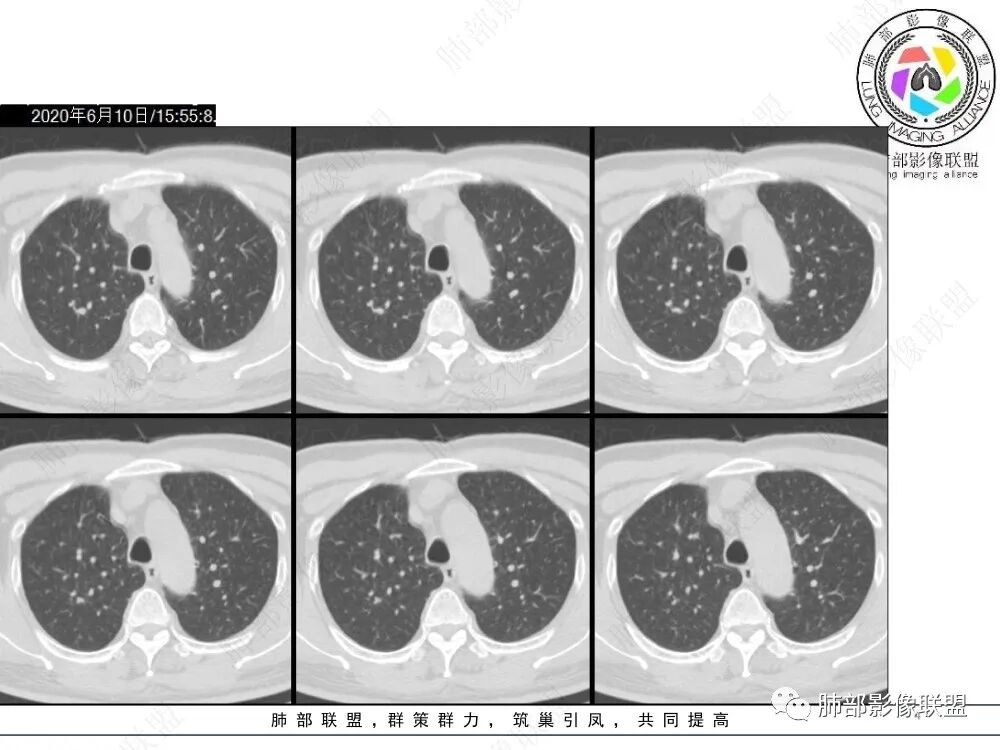

病例资料

影像与临床

1、老年男性,4天前受凉后咳嗽、咳痰伴胸痛。

2、既往高血压史、吸烟史。

3、右肺上叶不规则实性密度为主结节影,可见浅分叶,边界隐约可辨,界面欠清晰。病灶密度欠均匀,边缘似可见磨玻璃影,未见钙化及卫星灶。

4、矢状位示病灶沿肺动脉长轴走形,边缘较平直;

5、未提供肺门及纵隔影像。肺门及纵隔淋巴结情况未知。

6、综合分析,右肺上叶单发实性小结节,浅分叶,边界隐约可辨,未能明确与支气管关系。病灶边界不够清晰游离(与邻近肺组织多有瓜葛),加之缺乏周边征象,硬化性肺细胞瘤等良性肿瘤可能性较小。

需要鉴别的是炎性病灶(如炎性肉芽肿)与恶性肿瘤。病灶较小,恶性征象不多(小支气管阻塞、深分叶及毛刺、清楚的磨玻璃晕,张力高等等),仓促定性,未免仓促,可以定期复查是否有变化,穿刺活检也可视为积极措施,唯病灶较小,幽深不测,难度较大。

7.注意:1)血管旁实性密度小结节有时易被“瞒天过海”2)不宜轻视任何一个肺部结节。